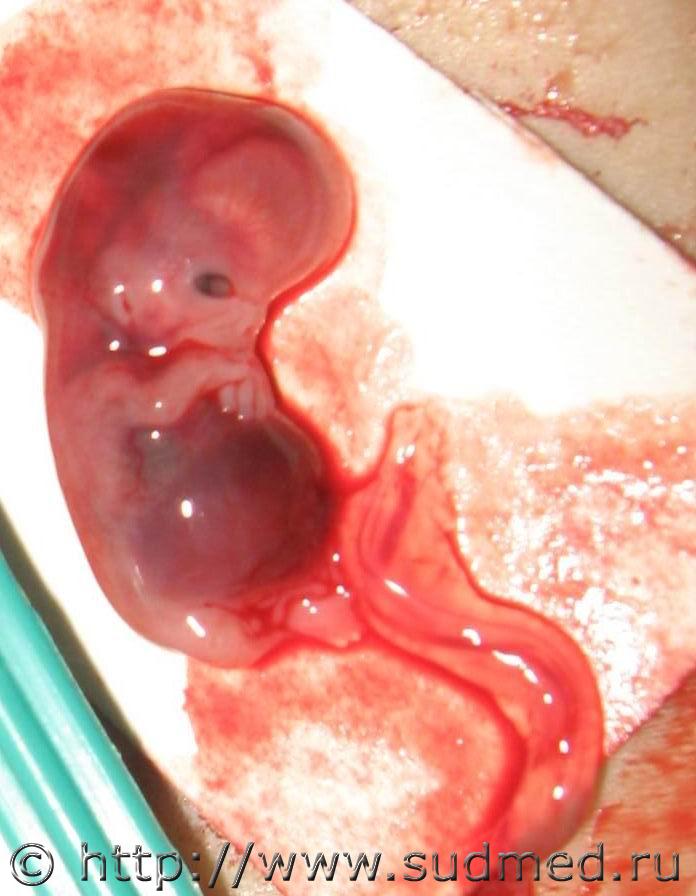

Эмбрион.

Вполне возможный повод для самоубийства молодой девушки.

Судебная медицина - Прикрепленное изображение Судебная медицина - Прикрепленное изображение